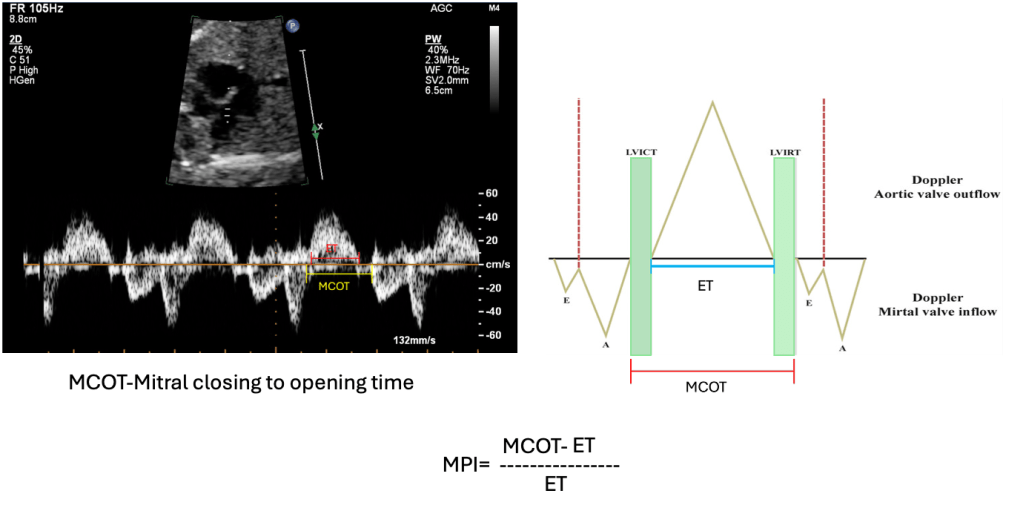

The Modified Myocardial Performance Index is a load-independent Doppler-derived metric that reflects combined systolic and diastolic myocardial performance by analysing key parts of the cardiac cycle:

The formula is: (IVCT+IVRT)/ET

The Modified Myocardial Performance Index is a term used when valve clicks are used as landmarks for measuring time intervals (Hernandez-Andrade et al.).